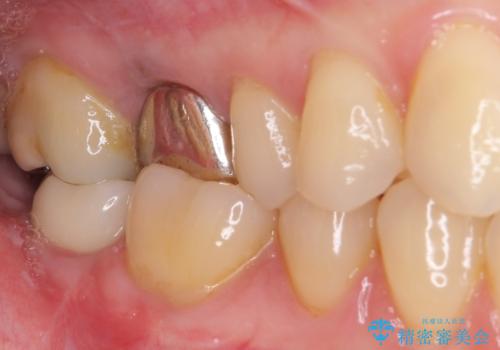

抜歯されたままの奥歯 ストローマンインプラントによる欠損補綴治療

ストローマン社のSLActiveというインプラントを使用し、インプラント埋入からクラウンが装着されるまで3ヶ月弱という短期間で終えることができました。

咬み心地はもちろん、清掃性もご自分の歯とほとんど変わらない状態となり、患者様には大変満足していただきました。